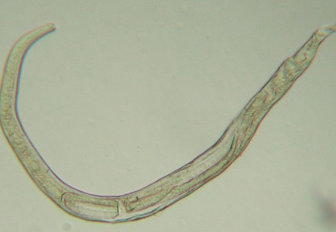

which animals is ollulanus tricuspis seen in? how is it transmitted?

cats only

cat-to-cat transmission through ingestion of vomitus

what gastric disease does ollulanus tricuspis cause in cats?

granulomatous gastritis

How is ollulanus tricuspis diagnosed in cats?

larvae detected in gastric juice or vomitus after centrifugation

find larvae or worms in histologic sections

CANNOT see on endoscopy (0.7mm -1.0mm in length)

how is ollulanus tricuspis treated?

fenbendazole 50mg/kg PO q24hrs x 5 days

which animals does physalopteria spp. infect? how is it transmitted?

dogs and cats

animals become infected after ingestion of insect intermediate host or vertebrate prey

most common in Midwest

How is physaloptera spp. diagnosed?

manual removal during endoscopy

found in vomitus or on endsocpy (3-6 cm in length)

how are physalopteria spp. infections treated?

-manual removal during endoscopy

-pryantel pamoate 20mg/kg PO every 2 weeks for 3 treatments

empirical therapy with an anthelminthic is warranted in cases of unexplained gastritis